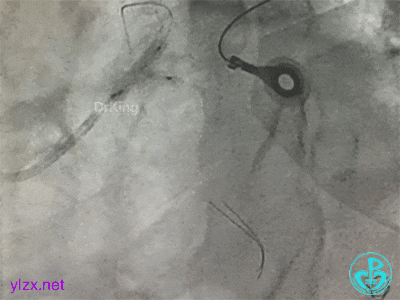

更换指引导管,导丝分别进入前降支和回旋支,球囊分别扩张前降支开口和回旋支开口,IVUS确认左主干及分支开口病变,前降支中段植入支架,对角支开口球囊扩张。

左主干分叉病变采取Crush双支架术式,回旋支开口植入支架,前降支开口球囊挤压后左主干到前降支植入支架(Crush双支架术式)。

导丝准备穿支架网眼Rewire回旋支时患者血压继续下降。去甲肾上腺素微量泵剂量逐渐增大至25ml/h,立即置入IABP,血压回升后再继续操作。